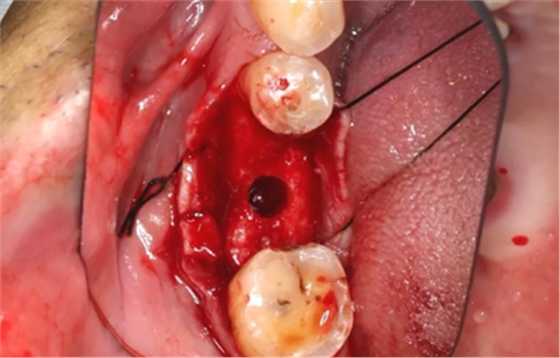

12、延期种植手术过程

使用直径3mm的环形取骨钻切取长约9mm的柱状骨标本,用于组织学和显微影像检查

(摄于2017年4月14日)

由于取骨致窝洞较大,加之缺牙间隙大,只好选择植入5mm直径种植体;种植备洞完成后,颊侧骨壁厚度仅约1mm。